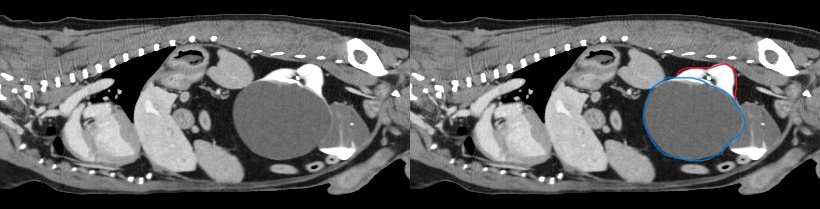

4) Cystic Kidney - incidental abdominal mass palpated during routine health exam

Blaze, 13 yr old chihuahua, was referred for surgery after his primary care veterinarian palpated an abdominal mass during a routine wellness exam. Abdominal radiographs were obtained, and a splenic mass was suspected.

We recommended additional diagnostics to identify the origin of the mass and to check for evidence of metastasis prior to an exploratory abdominal procedure.

Abdominal and thoracic studies pre and post contrast were obtained. Whilst the spleen appeared to be free of disease, the 3D renderings clearly showed a deformed left kidney. Review of the axial images showed a large abdominal mass originating from the left kidney. The right kidney appeared free from disease. No evidence of metastasis was detected within the chest or abdominal lymph nodes. The only abnormalities on lab work included mild elevations of ALT and BUN. Blaze was taken to surgery, where his left kidney was surgically removed. Histopathology confirmed the mass as a benign cystic structure.